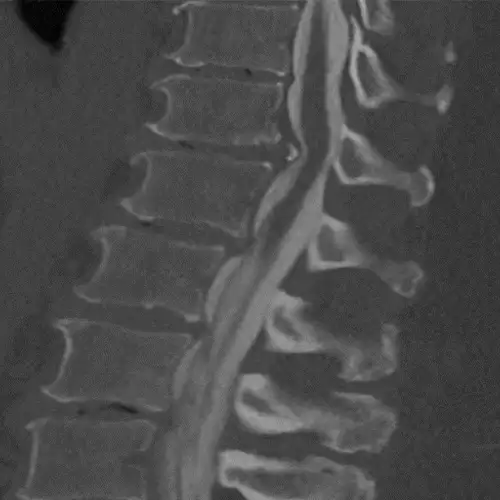

The diagnosis, in addition to being based on the symptoms and the physical examination by the specialist, is made like almost any spinal disease by means of magnetic resonance imaging (MRI), although it is usually complemented by computerized tomography (CT) and X-rays (Rx).

Sometimes contrast can be added to the intradural space in the CT and images of the spinal cord contour can be obtained (myelo-CT).